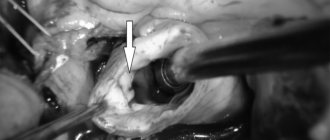

Далее по проводнику к месту, которое было суженным до раздувания баллона заводится такой же баллон, на поверхности которого закреплен стент в сложенном состоянии. Баллон раздувается, стент расправляется и «вжимается» в стенку артерии. Не всегда стент расправляется идеально и тогда нужен завершающий этап процедуры — постдилатация (по простому — додувание).

«Додуваем»

Внутрь имплантированного стента заводится жесткий баллон и раздувается большим давлением (до 25 атмосфер). Чаще всего после этого стент расправляется и хорошо прилегает к стенкам артерии.